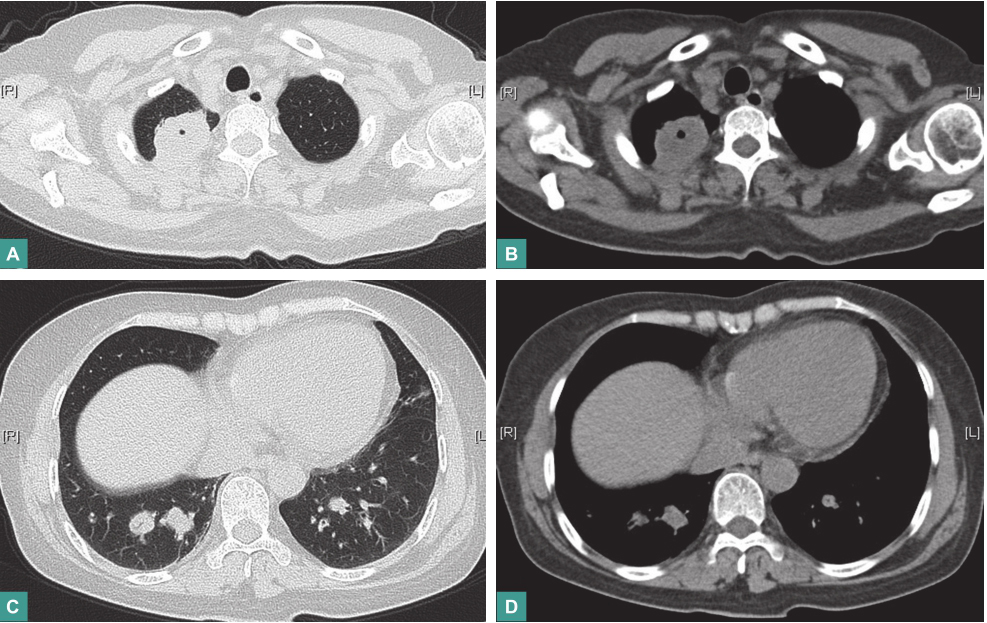

(5)影像学检查

胸部CT:①右肺上叶尖段占位病变,大小约4.0cm×3.1cm,较前明显增大,其内可见空洞;②双侧肺门区及周围新增多发结节状密度增浓影;③纵隔内多发淋巴结肿大(图5)。

图5 胸部CT表现

第一次冲击治疗后复查:

血沉42mm/h,C反应蛋白8.10mg/L。胸部CT:右肺上叶尖段占位病变较前明显缩小,双侧肺门区及周围多发结节状密度增浓影较前有所缩小,纵隔内多发小淋巴结较前有所缩小(图7)。

图7 第一次冲击治疗后复查胸部CT表现

第二次冲击治疗后复查:

血沉23mm/h,C反应蛋白8.94mg/L。胸部CT:右肺上叶尖段占位病变较前明显缩小,双侧肺门区及周围多发结节状密度增浓影较前有所缩小,纵隔内多发小淋巴结较前有所缩小(图8)。

图8 第二次冲击治疗后复查胸部CT表现